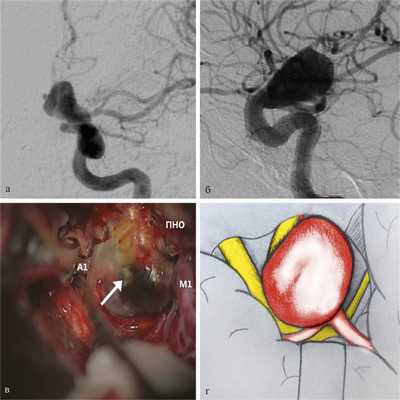

Передние (верхние) аневризмы. Передние аневризмы составили 21% от всех больших и гигантских параклиноидных аневризм [2]. Данные аневризмы формируются из передней (верхней) стенки ВСА с направлением купола вверх. Отличительным хирургическим признаком аневризм этой локализации служит расположение купола над зрительным нер-вом, поэтому зрительные нарушения у таких пациентов встречаются редко. В то же время шейка аневризмы передней локализации может быть связана с ПНО и ипсилатеральным зрительным нервом, вызывая его натяжение и компрессию. Важно учитывать, что аневризмы передней локализации могут быть спаяны с базальными отделами лобной доли, что при тракции может спровоцировать интраоперационный разрыв. В этой связи для уменьшения тракционного воздействия на лобную долю первоначально рекомендуется препаровка сильвиевой щели и выход на М1-сегмент СМА с последующим ретроградным выделением ВСА. Для клипирования таких аневризм резекция ПНО требуется редко. Применяется стандартное клипирование шейки аневризмы прямыми или изогнутыми клипсами вдоль верхней стенки ВСА (рис. 4).

Рис. 4. Параклиноидная аневризма переднего (верхнего) расположения. а — ЦАГ, прямая проекция; б — ЦАГ, боковая проекция; в — операционный вид (ПНО — передний наклоненный отросток; А1 — сегмент ПМА; М1 — сегмент СМА; стрелкой обозначено тело аневризмы); г — схема операционной картины: купол аневризмы направлен вверх, ВСА, ПМА и СМА находятся под аневризмой.